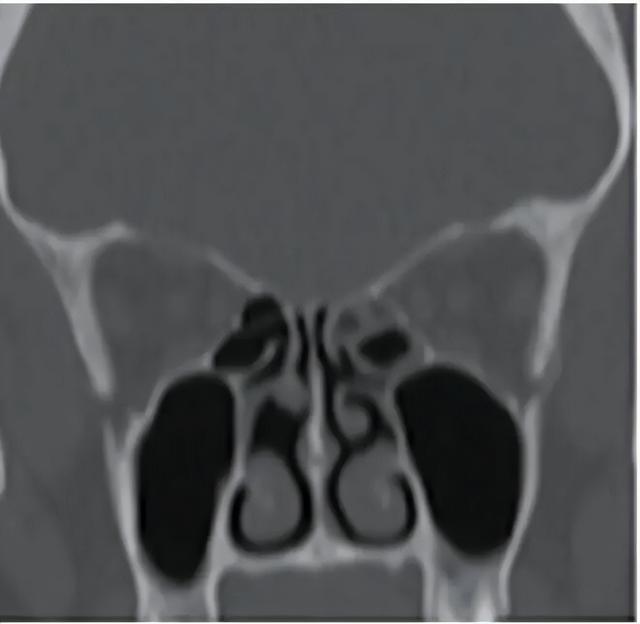

一位挖鼻癖患者的鼻窦鼻腔 CT,显示中鼻甲头部缺失。图源:参考文献[6]

在一项研究[5]中,37 名确诊挖鼻癖的患者中,有 32 人出现鼻中隔穿孔,占 86.5%。这种损伤会导致鼻腔气流改变,进而出现结痂、鼻塞、鼻出血、面部不适甚至“吹口哨样”气流声等症状。

病例研究还显示,挖鼻癖往往与精神心理问题有关,例如焦虑障碍、强迫症或其他精神疾病。在部分患者中,反复挖鼻甚至会造成鼻甲损伤、鼻中隔穿孔等结构性破坏。[6]